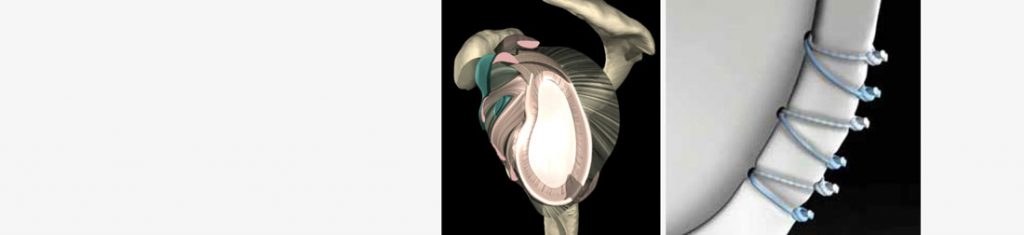

Die Rotatorenmanschette ist für die muskuläre Führung des Schultergelenkes von entscheidender Bedeutung. Rupturen können durch Stürze ausgelöst werden und treten meist im Alter über 50 Jahren in Folge von Verschleißprozessen auf.

Ob eine gerissene Sehne refixiert werden kann, hängt nicht nur vom Patientenalter, sondern auch von der biologischen Qualität der Sehne ab. Durch eine MRT-Untersuchung kann festgestellt werden, ob im individuellen Fall, eine operative Therapie erfolgsversprechend ist. In der Regel kann durch ein arthroskopisches Operationsverfahren die Sehne mit speziellen Nahtankern reinseriert werden.